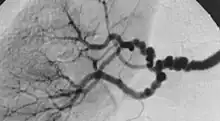

| The "string-of-beads" feature in multi-focal fibromuscular dysplasia. The sign is caused by areas of relative stenoses alternating with small aneurysms. | |

Multi-focal (previously known as medial) fibroplasia involves thickening of the media and collagen formation. It is typically reported as having the appearance of a "string of beads" on angiographic review.[4] "The 'bead' component is often larger than the normal arterial lumen, and in a subset of patients with FMD, aneurysms are present that may require treatment."[4] The multi-focal subtype of FMD accounts for nearly 80% to 90% of all FMD cases.[4]